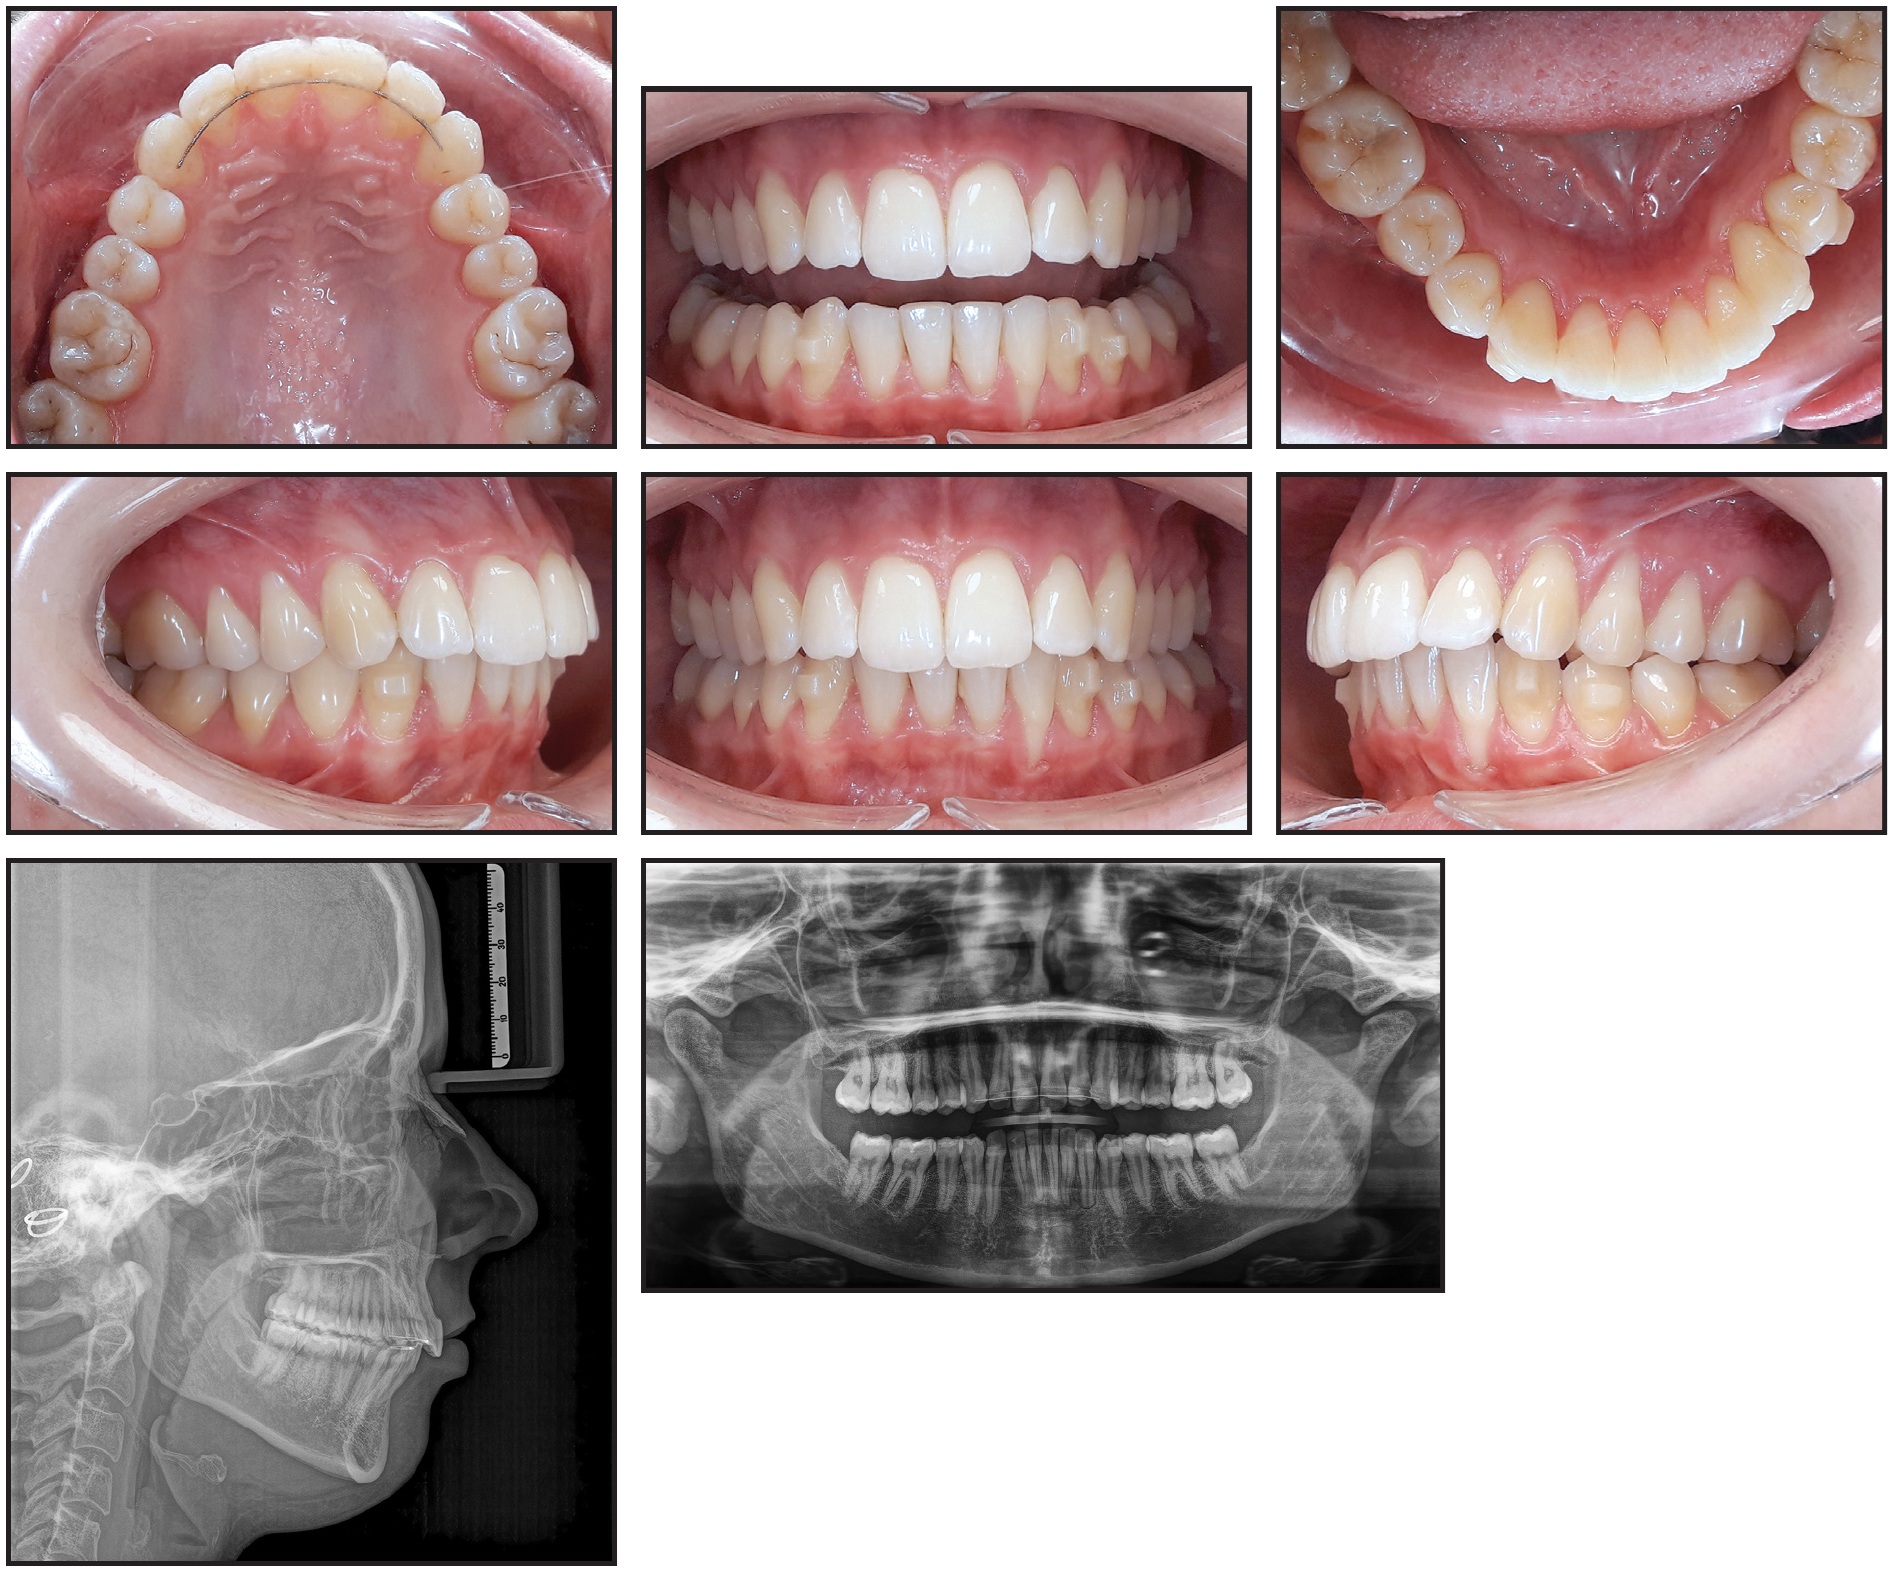

A 32-year-old female who had previously undergone successful orthodontic treatment elsewhere presented to our practice with the chief complaint of a protrusive lower left canine (Fig. 1). Multistranded-wire lingual retainers had been bonded to the upper and lower incisors and canines. One year prior to our consultation, the retainer wire had come loose from the lower left canine, but it had been reattached before the patient noticed any changes in tooth position. The patient reported that within six months of rebonding, however, the lower left canine had moved significantly.

Clinical examination found a bilateral Class I occlusion with an open bite in the region of the lower left canine cusp, resulting in an asymmetrical lower arch due to the protrusion of the lower left incisors and proclination of the lower left canine. This proclination had caused the contours of the canine root to become visible on the lingual side. Gingival recession of 5mm, with no apparent inflammation, was noted on the buccal side of the lower left lateral incisor.

Fig. 1 32-year-old female patient with severe protrusion of lower left central incisor, lateral incisor, and canine due to failure of fixed lingual retainer, before retreatment.

The panoramic radiograph confirmed the patient’s overall dental and periodontal health. Cephalometric analysis (Table 1) indicated a skeletal Class II malocclusion due to a retrognathic mandible (SNB = 72.5°) and a vertical facial type (SN/Me-Go = 39°), along with retroclination of the maxillary base and a steep occlusal plane. The upper incisors were retroclined (U1-SN = 94°), and the lower incisors proclined (L1/Me-Go = 101°), while both were forwardly positioned (NPog-U1 = 18mm, NPog-L1 = 11mm), forming a convex lip profile.